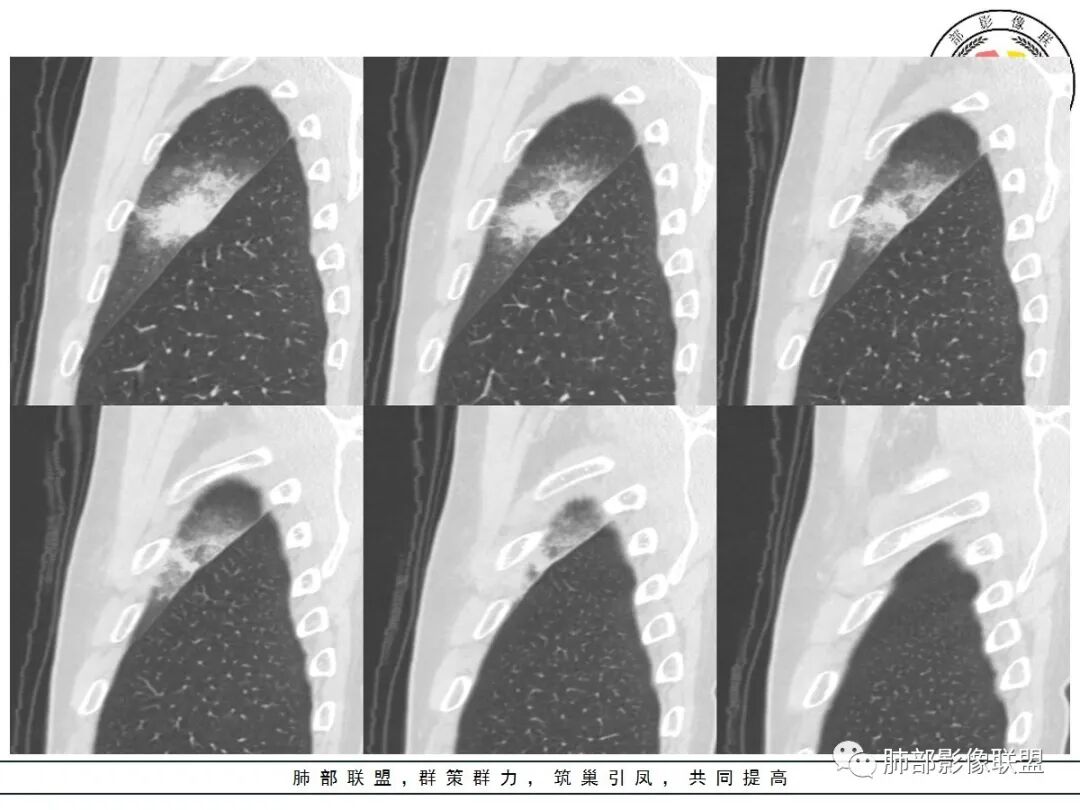

我标示一下,尖后段搭到一部分,前段也占了一点点。

主体在舌段

有占位效应吗?

有,斜裂局部膨隆

边缘膨隆,叶间裂有局部膨出下坠

有膨隆+收缩

密度?

实变为主,加周围模糊GGO

GGO+实变

南边:

强化如何?

强化有疑问,前面感觉有低密度的,有些图好像又均匀

不均匀中度强化

不均匀轻中度渐进强化。

整体形态

切面所致,要看长轴

外围大,内带小